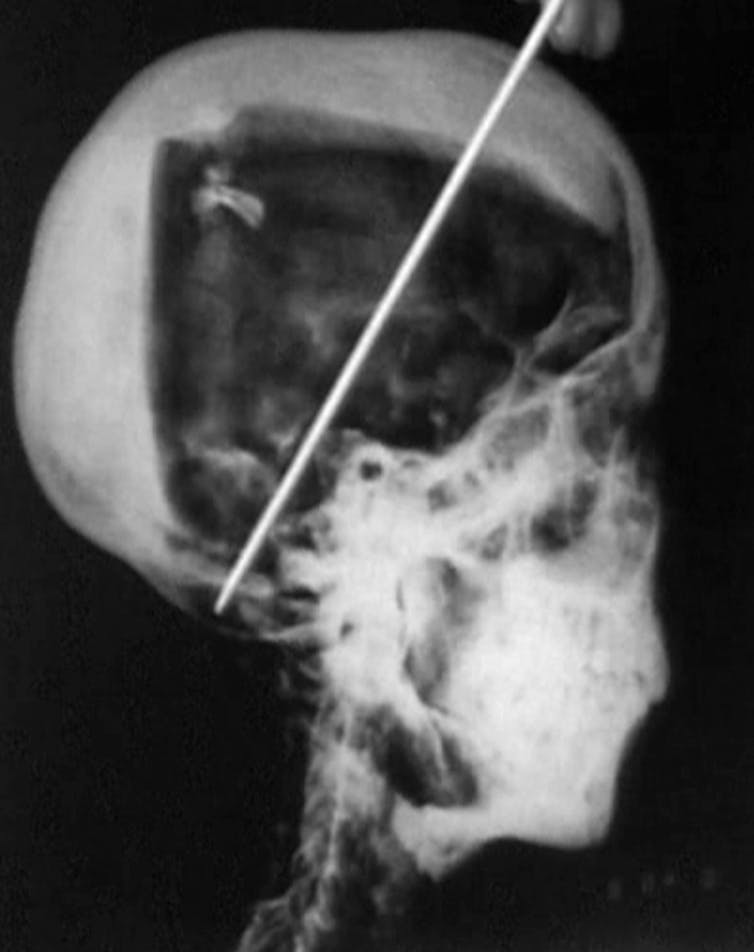

Les analyses débutèrent en 1968, les premiers rayons X révélant une anomalie à l’arrière du crâne, ainsi que la présence de fragments osseux dissociés (déjà remarqués dans les années 1920) : les conséquences d’un choc généré par un objet contondant ? La preuve d’un meurtre sordide, fomenté par l’intrigant vizir Ay, qui lui succède sur le trône alors que la XVIIIᵉ dynastie touche à sa fin ? Ce forfait aurait ensuite été masqué par un excès de résine…

Des investigations plus poussées ont ensuite démontré que l’enfoncement osseux constaté avait bien eu lieu, mais après le décès, probablement lors des étapes d’embaumement… Peut-être même lors des premiers examens qui ont suivis la découverte.